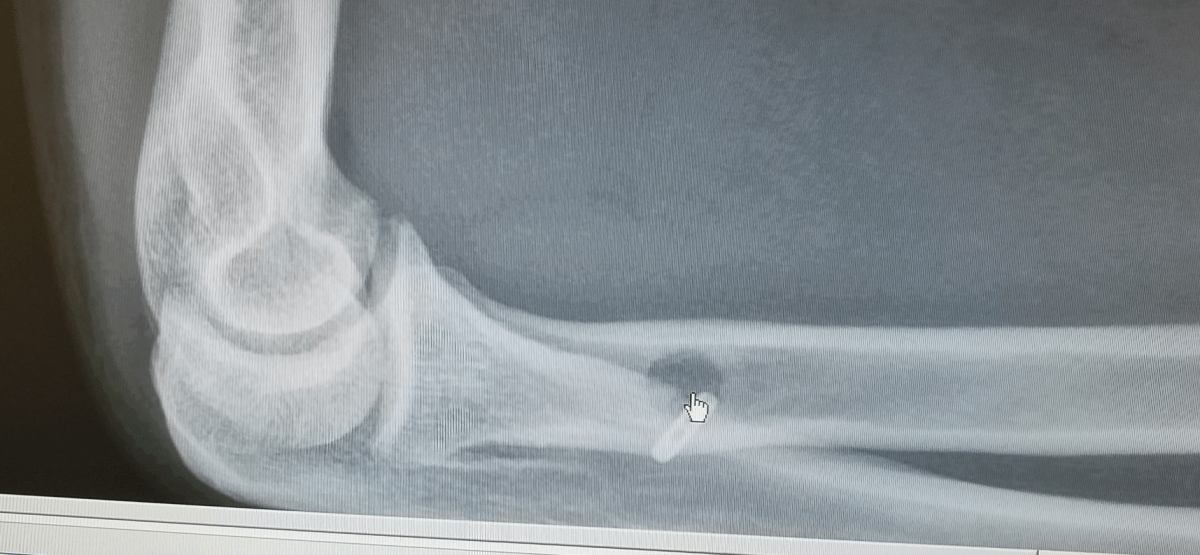

Last week while helping my wife load a household appliance we were donating into her aunt’s pickup was the sickening sound of my right bicep detaching itself from the elbow distal tendon. The pain was bad, of course, but the realization of the extent of the injury was worse. Suddenly plans of completing a 3rd consecutive DirtyKanza were nixed. In addition to a surgical reattachment, performed yesterday, there’s several months of recovery and rehab before I can return to riding once again.